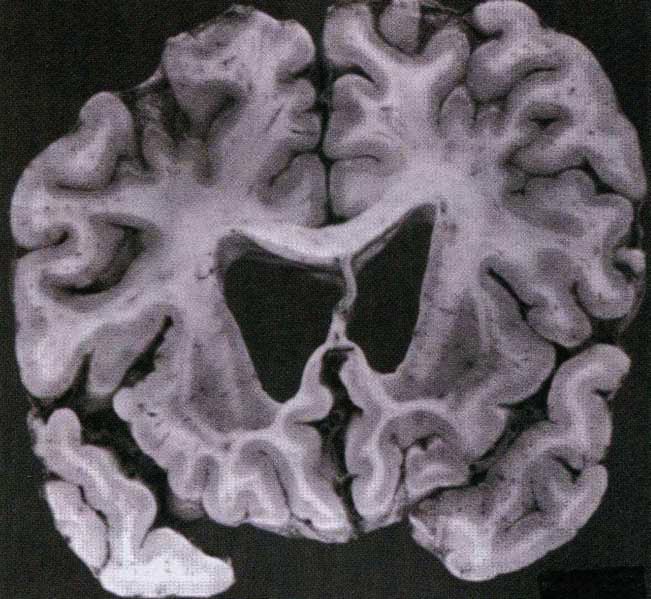

Huntington Disease - Marked Caudate Atrophy